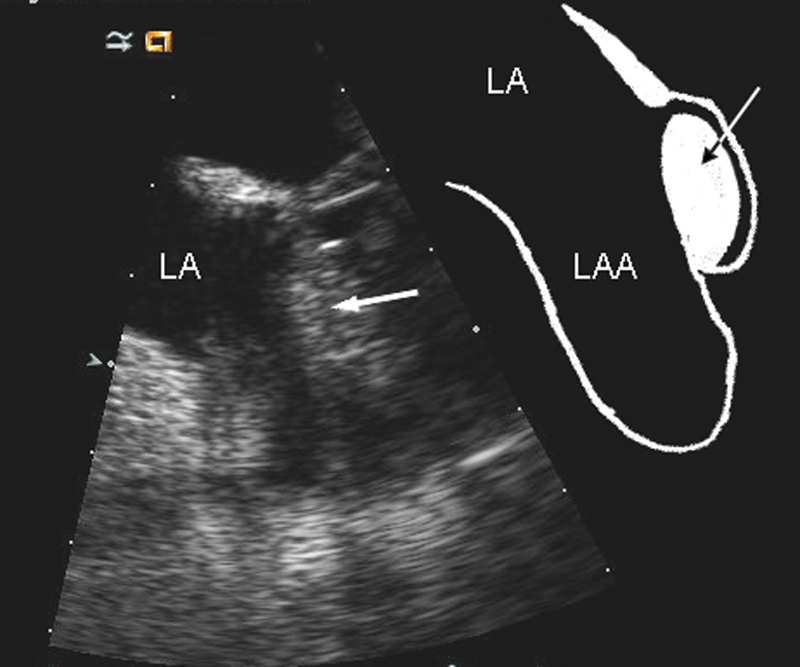

فحوصات تشخيصية لبعض امراض القلب والشرايين التاجية